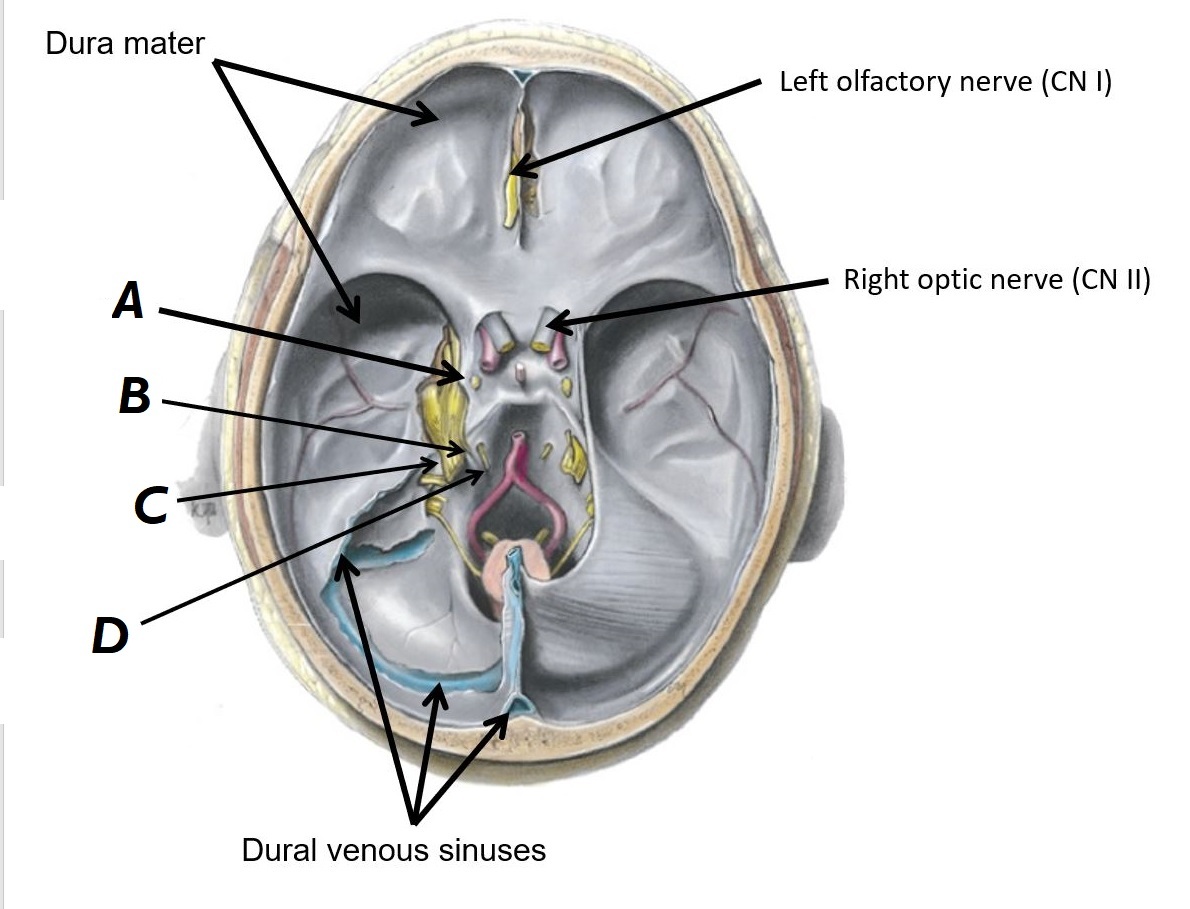

Name structures A to D

A - Optic chiasm

B - Left internal carotid artery

C - Basilar artery

D - Left vertebral artery

Name nerves A to D

A - CN III (occulomotor nerve)

B - CN IV (trochlear nerve)

C - CN V (trigeminal nerve)

D - CN VI (abducens nerve)